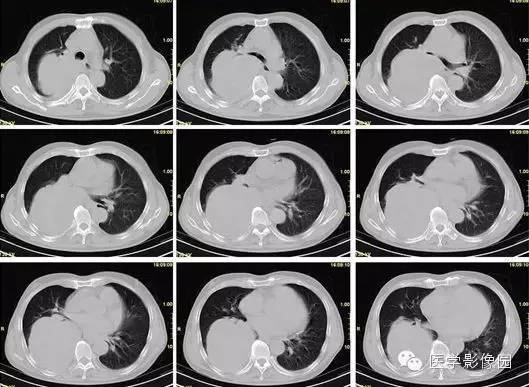

【病例】巨大中央型肺癌1例